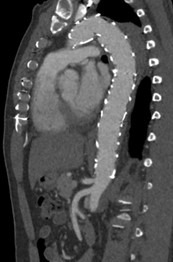

Fig. 1-4: Chronic residual type B dissection after ascending repair. Follow-up CT examination demonstrates TEVAR in descending thoracic aorta extending to the level of the celiac trunk with thrombosis of the false lumen and aortic remodeling due to FLO in false lumen. The FLO is completely collapsed in the FL due to depressurize the false lumen.